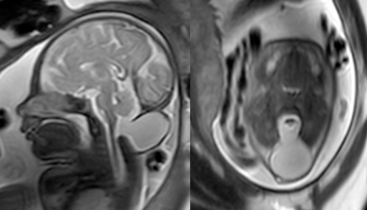

A: occipital meningocele diagnosed prenatally; B: moderate-size meningocele at birth; C: tonsillar herniation on MR at 4 months; D: increased volume of meningocele at surgery - encéphalocèle occipitale supra-tentorielle, épidermisée ou non

- malformation du cervelet de type Chiari 3, possiblement de constitution secondaire cf. cas ci-dessous

encéphalocèle occipitale associée à des malformations multiples du tronc cérébral et de l’encéphale ; noter l’hypoplasie mandibulaire : syndrome de Pierre Robin d’origine centrale, absence de ventilation spontanée à la naissance. - malformations rachidiennes de type Klippel-Feil et hémivertèbres